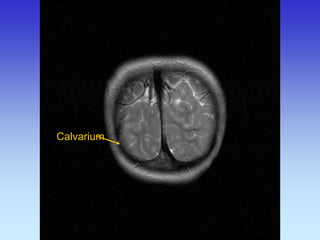

Calvarium

Falx cerebri